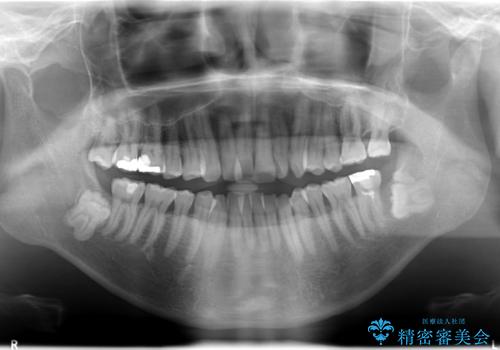

インビザライン invisalign ガタつきを治すマウスピース矯正

- 非抜歯・上顎臼歯遠心移動によるマウスピース矯正を計画した。

ガタつきを取り除くだけであれば非常に簡潔であるマウスピース矯正ですが、奥歯の位置関係の是正や、垂直的な歯の位置のコントロールなどが計画に含まれる場合、治療が難しくなってきます。